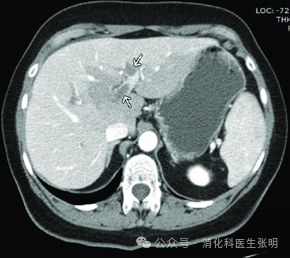

图片

门静脉主干内的血栓